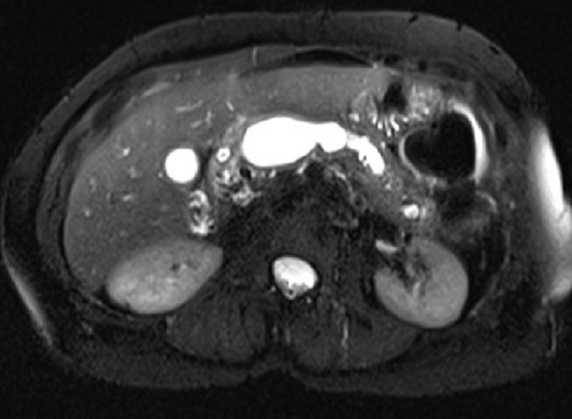

Aspect

radiologique de dfilatation/stenose du canal

pancreatique principale d'une pancreatite chronique

avancee tardive ( fleche rouge ) .Image IRM encoupe

axiale a ponderation sur T2 . Parenchyme du pancreas

est atrophique et hyperintense .. |